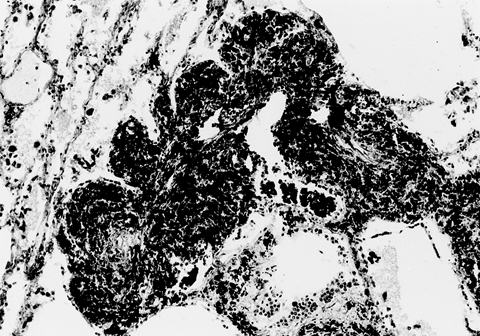

病理特征:在轻度尘肺的基础上出现类风湿性尘肺结节,其早期为胶原纤维增生,很快转为特殊性坏死,围绕坏死的核心发生成纤维细胞炎性反应而形成类风湿肉芽肿。大结节一般由数个小结节组成,每个结节轮廓清楚,最外为共有的多层胶原纤维所包绕。病理检查结节直径在3mm~20mm之间,融合可达50mm以上。结节切面呈一种特殊的明暗相间的多层同心圆排列。浅色区多为活动性炎症,而暗区则为坏死带,较暗区多是煤尘蓄积带。

Caplan综合征(类风湿性尘肺结节)

临床表现:患者临床症状和呼吸系统症状较少,只有少数病例肺功能具有不同程度损害。胸部X线表现为两肺可见散在的圆形或类圆形、密度均匀的结节,直径在0.5mm~5cm。结节的分布没有规律,可为单发,更多的为多发。注意与结核球、转移性肺癌、叁期尘肺等病鉴别。